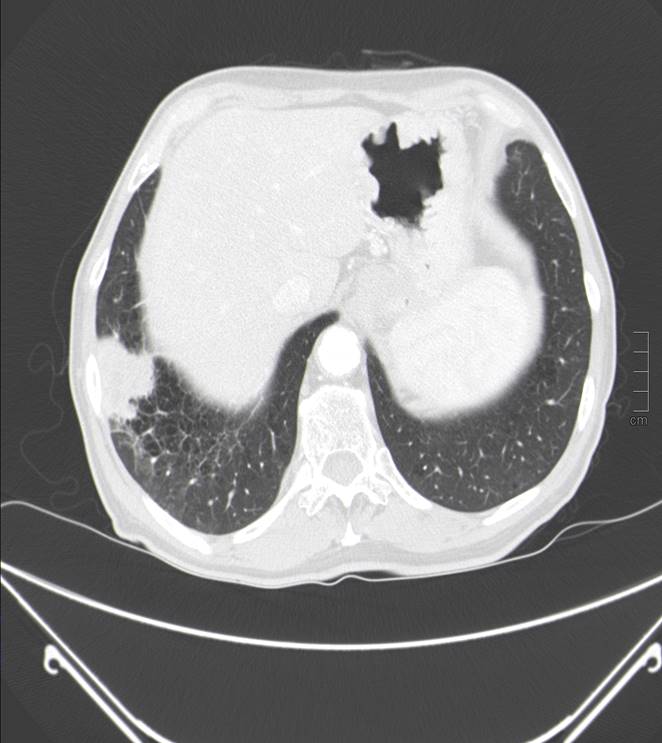

Masa en lóbulo inferior derecho (LID), compatible con neoplasia primaria pulmonar.